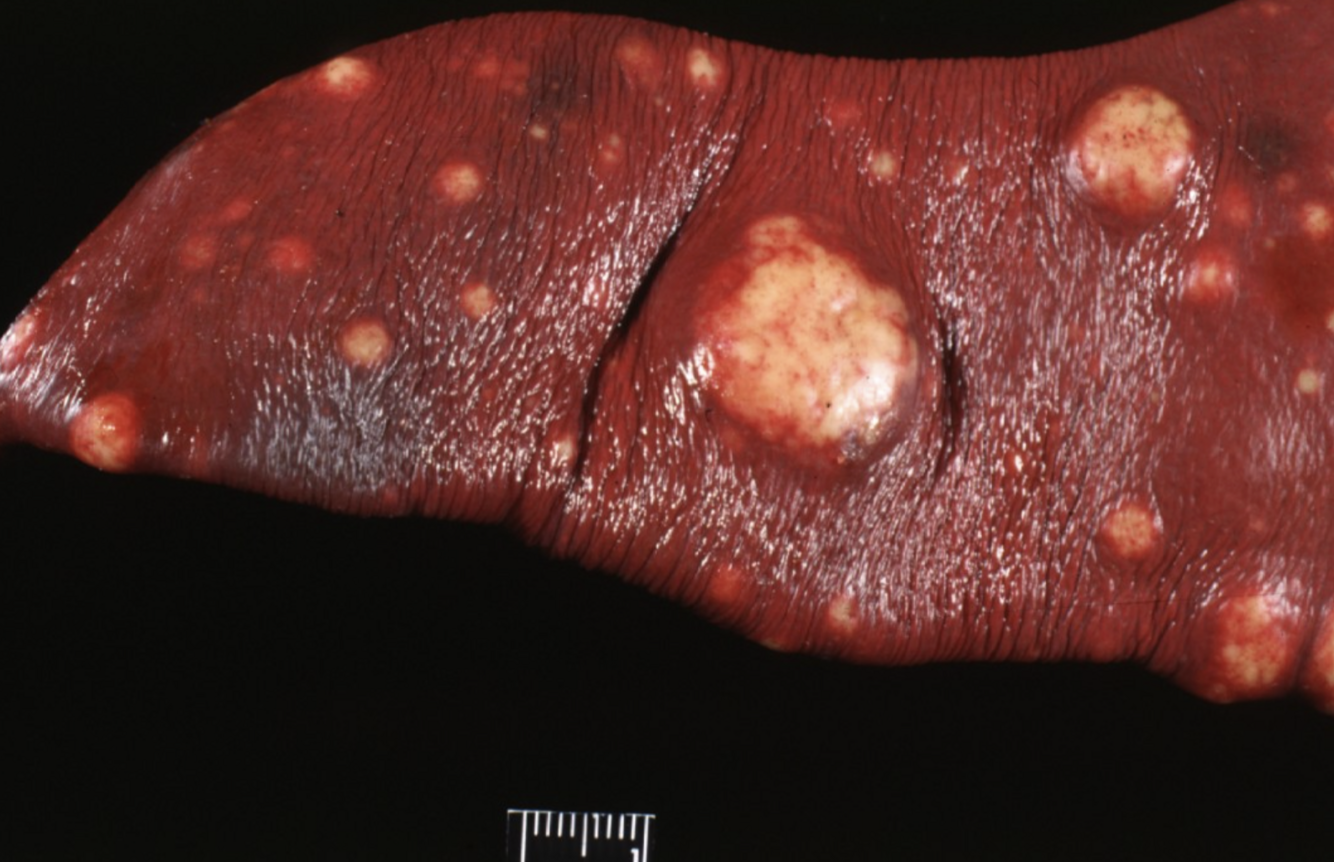

Histology each of these white nodules shows iinfiltrations of poorly differentiated epithelial cells with marked nuclear atypia and a high mitotic rate.

Which diagnosis is most appropriate?

a.Primary splenic carcinoma

b.Splenic nodular hyperplasia

c.Metastatic carcinoma

d.Haemangiosarcoma

A

Metastatic carcinoma

metastatic carcinoma is a type of cancer that orginates in epithelial cells, that has spread from the primary site to other parts of the body.